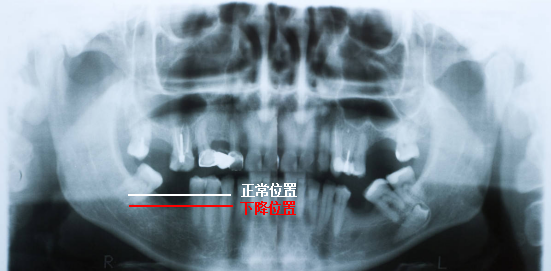

🔎牙周情况

通常来说,健康的牙槽骨的牙齿周围是被牙龈包裹住没有很大缝隙的,牙间缝隙较大而且是黑色阴影,牙齿整体比较长,多半是牙周炎,且牙槽骨情况也不好。

X光拍片为什么要等看牙为什么要拍片?非专业人士如何看懂自己的牙片!_https://www.jmylbn.com_新闻资讯_第12张

△正常情况下,牙槽骨高度位于牙根与牙冠的交界处下方一点(白色线标注位置)。